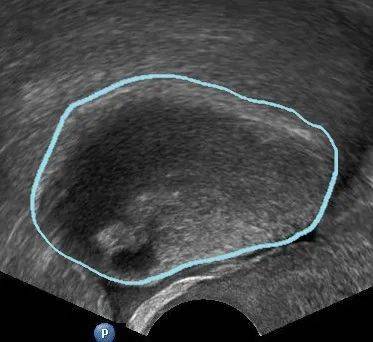

2、黄体囊肿

黄体囊肿多发生于月经周期的后段(第14~28天),由于这种囊肿会持续分泌孕激素,可能导致月经推迟。

一般来说黄体囊肿会自行消退。但极少数会发生破裂,引发下腹疼痛和盆腔内出血,此时需要及时就医,根据 严重程度来决定保守治疗或手术治疗。